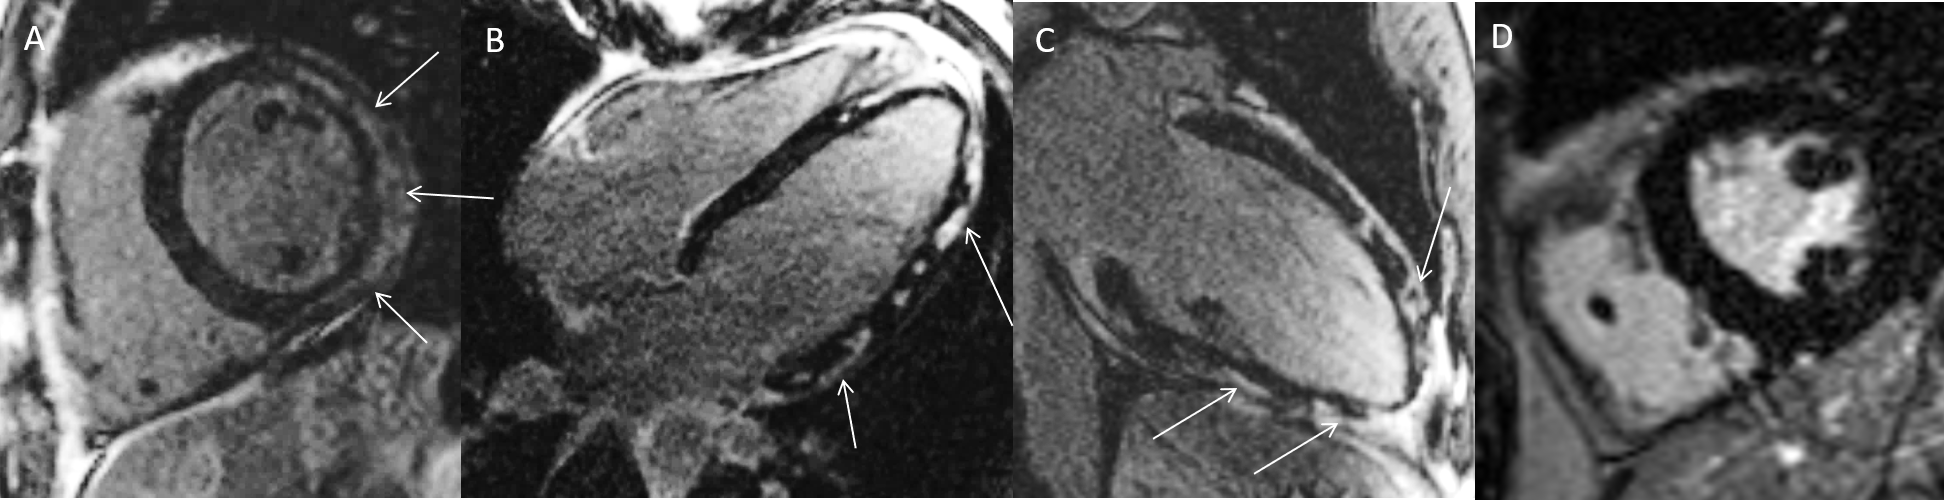

MRT Aufnahme mit Kontrastmittel

Patient mit Schmerzen in der Brust, ST-Hebungen im EKG sowie deutlich erhöhten Herzenzymen. In der Herzkatheteruntersuchung keine Engstellen. Im CMR Nachweis von mehreren hellen Arealen (Pfeile) in den Spätaufnahmen nach Kontrastmittelgabe (=Late Enhancement) passend zu einer Herzmuskelentzündung = Myokarditis (A-C).D = Gesunder Vergleichspatient (gesunder Herzmuskel stellt sich in den Spätaufnahmen dunkel dar).